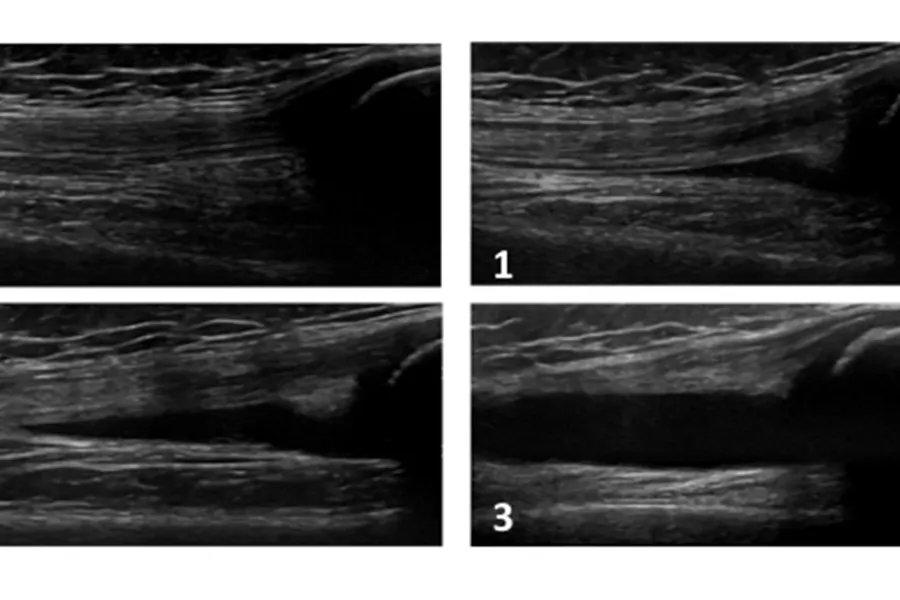

Atlas og instruksjonsvideoer til bruk for ultralydundersøkelse av barn i forskjellige aldersgrupper. Atlasene og instruksjonsvideoene er utarbeidet i forbindelse med MinJIA-studien av Nina Krafft Sande og kolleger.

Ultralydatlas